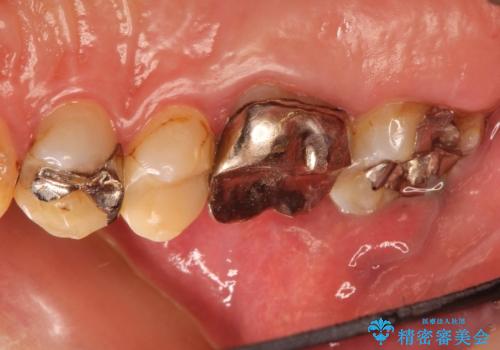

金属だらけの奥歯 根管治療のやり直しとセラミック化

- 神経のある歯を先にセラミック修復し、その後根管治療のやり直しを行う

インレー(詰め物)は、神経を保存したまま上部を丁寧にやり替えます。

神経の無い歯のクラウン(かぶせ物)は、根管治療を顕微鏡下でしっかりとやり直し、その後に土台の築造とかぶせ物の製作を行うことで今後問題が生じる可能性を可及的に低くできます。